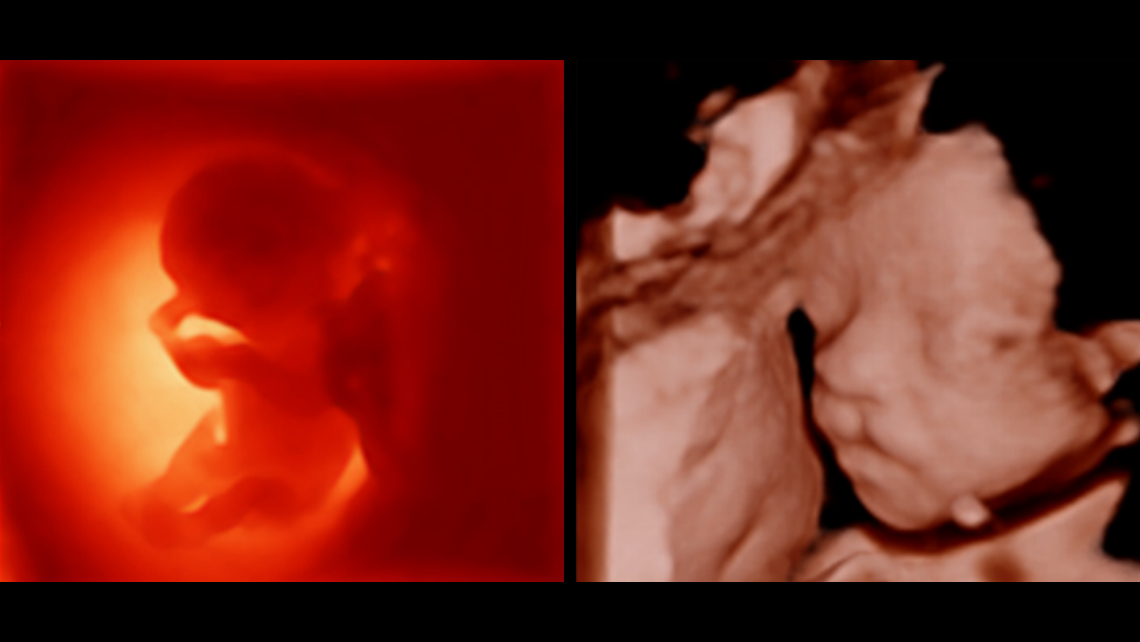

Images cliniques